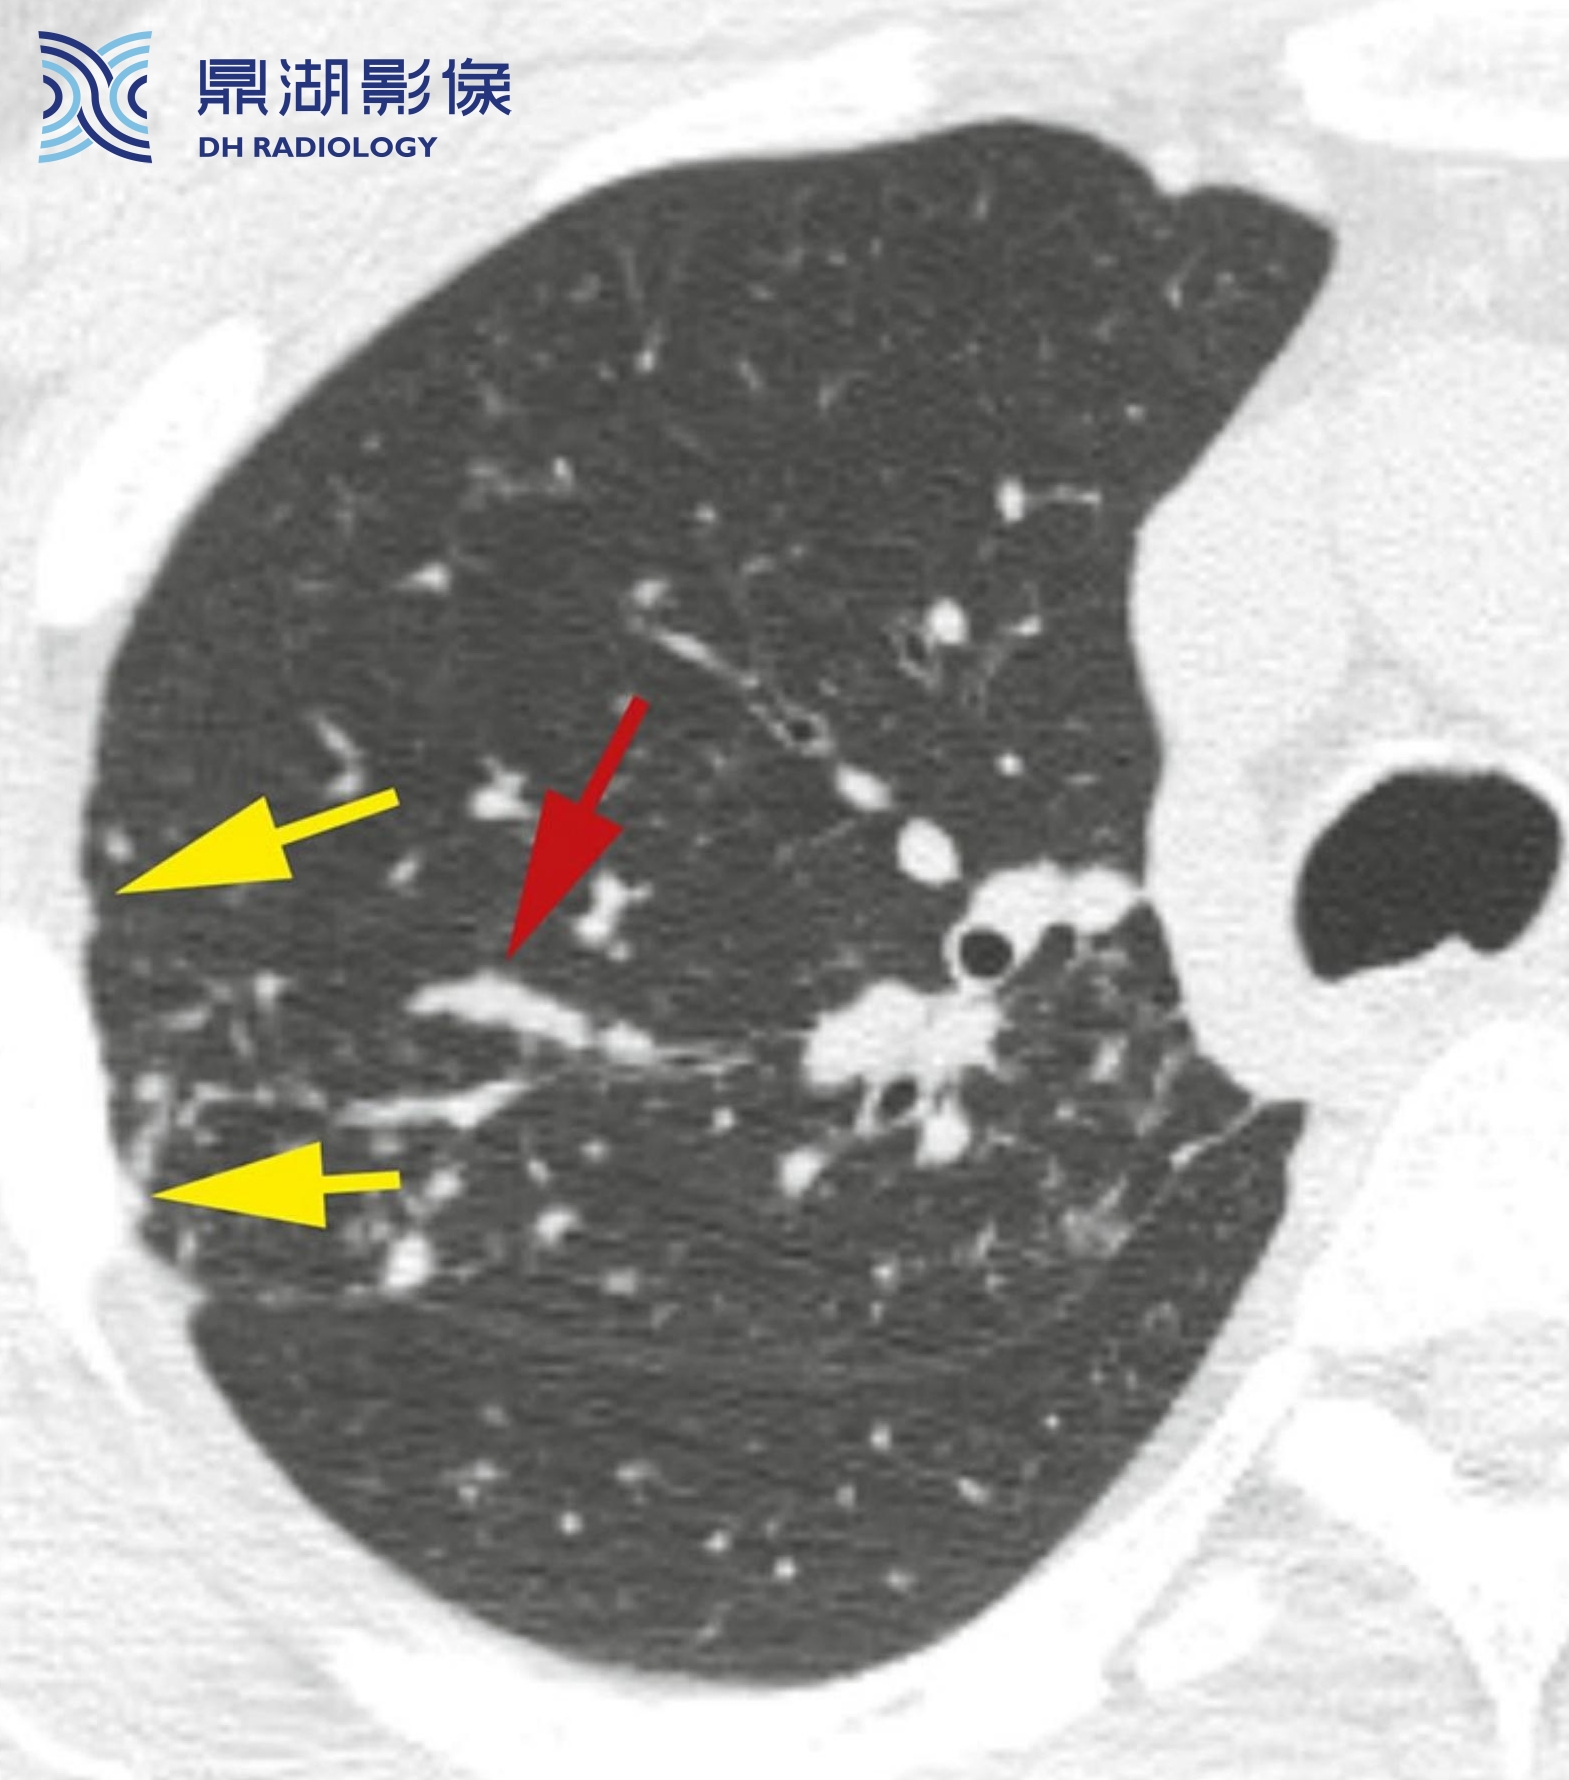

4c3490966e64a4453dcb6053827bc11b.png

结节病伴小叶中心性结节。结节主要分布于小叶中心且边界模糊(红箭)。胸膜下可见数个散在结节(黄箭,B)。支气管血管周围间质延伸至肺外周,与小叶中心支气管和动脉相连。在一些患者中,结节病肉芽肿主要累及上述结构,形成边界清楚或模糊的小叶中心性结节。

上述这种表现为小叶中心性结节的结节病,与结核较难鉴别。